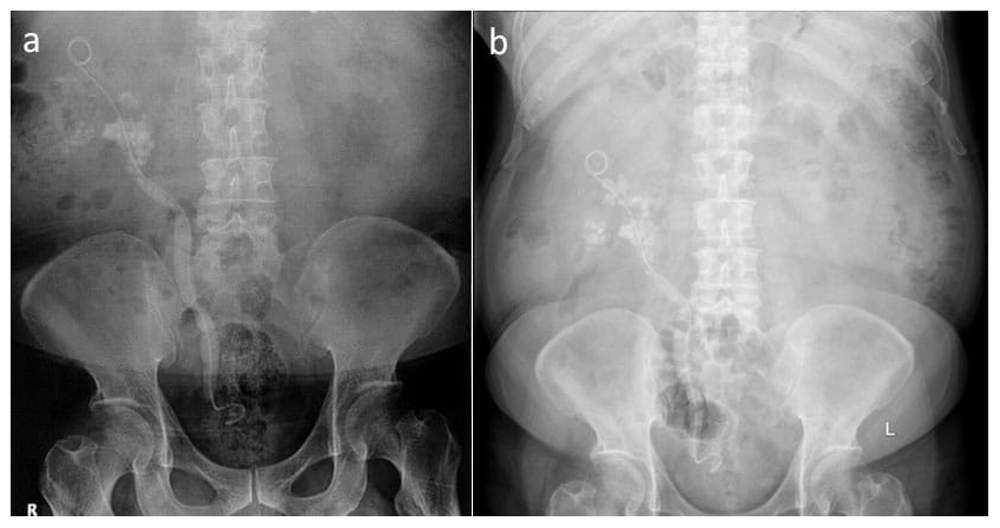

Computed tomography (CT) urography at the previous hospital showed a staghorn stone at the right inferior calyx with a size of 45.7 × 59.3 × 27.5 mm (Hounsfield unit not available), a left renal cyst with size of 19.2 × 22.2 × 18.9 mm, and a third-grade right-side hydronephrosis (Figure 1). Post-RIRS photo showed a double J stent with multiple tiny stones from the right pelvio-calyces to vesico-ureteral junction (Figure 2a).

An immediate (a) and 1 month (April 2016) (b) Plain abdominal photo following retrograde intrarenal surgery shows multiple tiny stones along the right genitourinary system.

A month later at when he come to our hospital for a second opinion, his plain abdominal X-ray result had not changed (Figure 2b). Right ureteroscopy (URS), right nephrostomy, and right PCNL was performed and post-operative X-ray imaging was conducted (Figure 3a). Another right URS was performed 2 weeks later, resulting in the remaining 8-mm stone at the ureter-pelvic junction (UPJ) (Figure 3b).